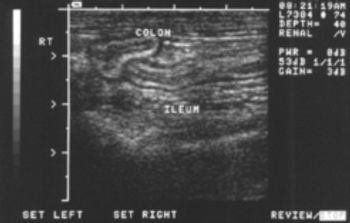

Join veterinary radiologist Dr. Kathy Spaulding on an ultrasonic tour of the intestinal tract and see which findings might indicate disease.